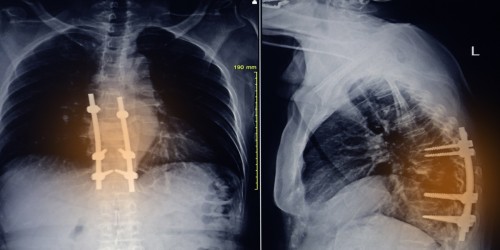

I have had 3 back surgeries in 1 month now. The first was a microdiscectomy/decompression of the lower lumbar. 1 week later I had a 2nd surgery to repair a spinal fluid leak. Following that surgery, fluid began to drain from incision. A 3rd surgery was done to further repair spinal fluid leak 1 week later. It has now been 8 days since last surgery in which a pin rose tube was placed next to incision sight. Fluid has streamed from the tube and is still slowly coming out of incision. It was confirmed that there was a minimal amount of bacteria in the incision and I was placed on iv antibiotics for 3 days and am now taking oral antibiotics. What is going on? Why won't it stop and what can I do to make it stop? Is this a common complication?